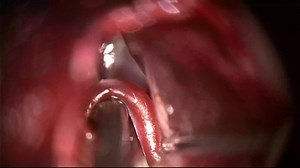

- Microvascular Decompression

Surgery - Microvascular Decompression

Trigeminal Nerve - Decompression

in Hemifacial Spasm - Vascular Decompression

Surgery - Facial Nerve

Decompression